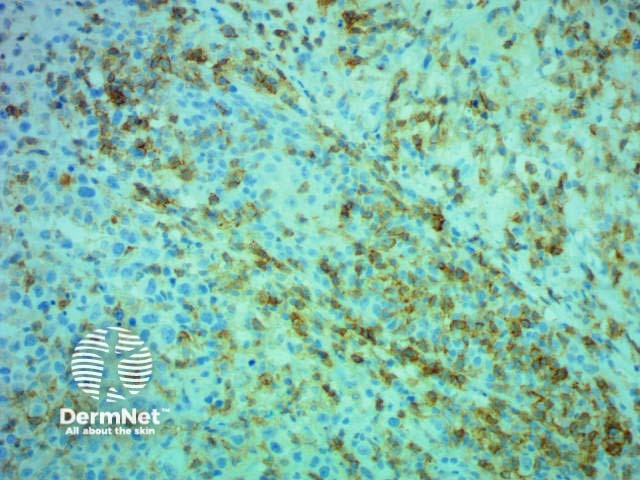

Mycosis fungoides, histology

Immunohistochemistry CD4 stain positive